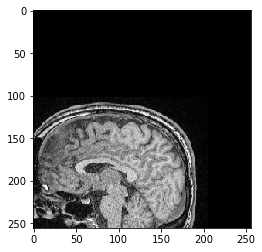

Nous allons maintenant extraire une tranche Z du jeu de données 3D et la visualiser. Dans le système 012, nous prenons une tranche de la pile dans la première dimension (indice 0). Elle a la position de tranche Z=100 (système ZYX) ou la position 100 le long de la dimension 0 (système 012).

slice = image[100]

cle.imshow(slice)